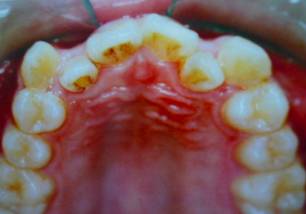

牙齿需要矫治的患者,往往牙齿和排列和咬合关系多会出现错乱,那些错乱的牙齿即使不拔除,它也是没有功能的,因为它和对颌的牙齿咬不上。

并且,这些排列不正常的牙齿很难清理干净,容易在它的周围存留很多食物残留,久而久之就形成蛀牙,最后也是一拔了之。我们医生拔牙的时候有一定选择的,一般是拔除那些坏牙、没有功能的牙。

一般来说,拔牙以后的牙缝可以被两个方面的牙齿移动所关闭,一个是前面不齐、前突的牙齿向拔牙间隙移动,占据部分拔牙间隙,还有就是后面的大牙也可以向关(拔牙间隙)移动,这样就可以关闭了这个间隙。

拔牙的目的是为了给前突、拥挤的牙齿提供足够的间隙,另外还用于调整牙齿的咬合关系。所以问题是:你牙齿间的这些可以用的空隙有多少?如果多,那就好办,不拔牙可以;如果少,那还是有可能要拔牙。